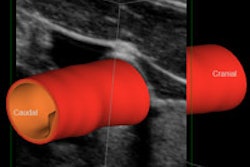

(A, above) Carotid plaque classified as Gray-Weale Type II shown with a B-mode and shear-wave elastography image. (B, below) The Young's modulus value of the plaque located in the anterior of the internal carotid artery was obtained using the Q-Box-Trace software tool. All images courtesy of the Journal of Ultrasound in Medicine.What's more, logistic regression and receiver operating characteristic (ROC) analysis suggested that the combination of the mean Young's modulus with stenosis rate could yield increased sensitivity and specificity for identifying symptomatic carotid plaques, according to the researchers.